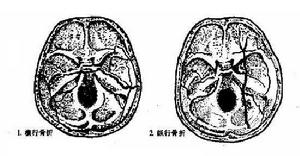

顱骨骨折多發生於顱底部,1/3的顱底骨折侵入顳骨岩部。依其骨折線分為縱行駛骨折、橫行骨折及岩尖骨折三類。縱行骨折最多見,橫行骨折居第二位,岩尖骨折最少見。縱行駛骨折預後較好。三類骨折同時出現。

(一)縱行骨折:多由於顳部或頂部受到撞擊所致。骨折線與岩部長軸平行,常自顳骨鱗部沿外耳道骨部的後上壁,經鼓室蓋在迷路前方,於膝狀神經節的前上部,順頸內動脈管到顱中窩底的棘孔或破裂孔。骨折線不貫穿骨迷路,故對內耳損傷機會較少,主要對中耳損害,常有聽小骨脫位或骨折。鼓室損傷,鼓膜未破時,鼓室內積血,鼓膜呈蘭色,唾液中可帶血。鼓膜破裂時,有血液自外道流出,如腦膜破裂,則有腦脊液耳漏。長期腦脊液耳漏可引起腦膜炎。中耳損傷時可出現傳音性耳聾。少數累及面神經,可出現面癱及舌前2/3味覺喪失。面癱多為暫時性。

(二)橫行骨折:主要由於枕部受到暴力所致。骨折線與岩骨長軸垂直,由顱底後窩橫過岩錐到顱中窩,多從枕骨大孔或頸靜脈窩,橫過內耳道和迷路到顱中窩的破裂孔或棘孔區。內耳損傷重,耳蝸及半規管內常有出血,迷路受損時有較重的眩暈、噁心、嘔吐,檢查可有傾倒及自發性眼球震顫,可持續數周,待對側代償後症狀消失。前庭功能檢查,患側功能喪失,聽力呈感音性耳聾。傷及中耳者較少,偶有迷路損傷同時中耳內壁也被震裂,導致蝸窗膜破裂,鼓室積血,約有半數並發麵癱,且為永久性癱瘓。